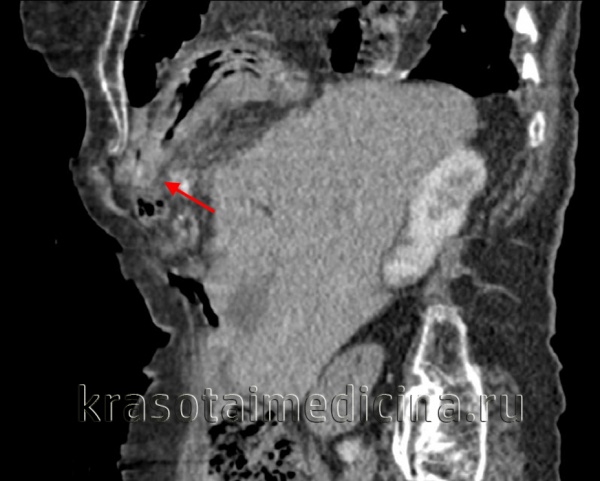

- Лучевая диагностика. Выполняется рентгенография и КТ грудной полости, КТ брюшной полости. Выявить разрыв на рентгенограмме можно только при пролапсе органов пищеварения в область грудной клетки. Для уточнения локализации травматического дефекта грудобрюшной перегородки, дифференциальной диагностики травмы и релаксации органа осуществляется контрастная рентгенография желудка либо ирригография. Просматривается желудок или петли кишечника в левой половине грудной клетки, определяется смещение пищевода.

КТ органов грудной клетки/брюшной полости. Травматический дефект в передних отделах диафрагмы справа с эвентрацией кишечника, сальника, кровеносных сосудов в грудную полость

- Ультразвуковое исследование.УЗИ ОБП и УЗИ плевральной полости даёт возможность подтвердить наличие диафрагмального дефекта, смещение ОБП, наличие свободной жидкости в обеих полостях. Наблюдается высокое стояние одного из куполов диафрагмы. Левосторонний разрыв сопровождается разъединением плевральных листков с появлением неоднородного содержимого между ними. При правостороннем дефекте обнаруживается необычно высокое расположение печени – её верхний край может находиться на уровне второго ребра.